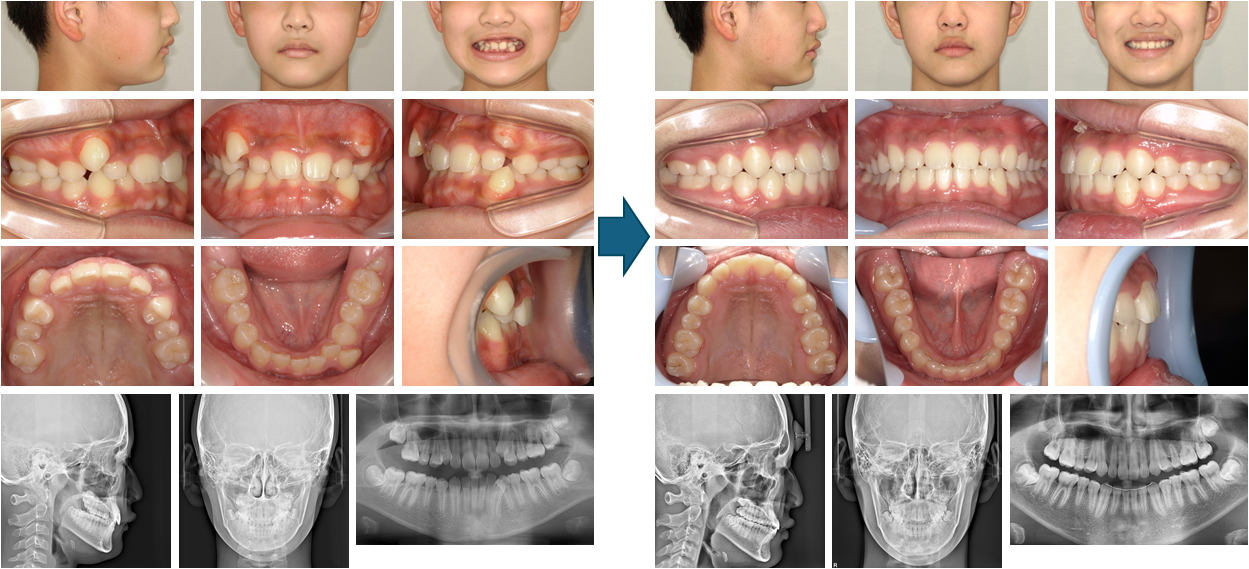

【治療例 K6440】初診時年齢:9歳4か月 / 性別:女性 / 主訴:上の歯が変な所から生えてきている、下の歯が生えてくるスペースが無い

治療の概要:上顎両側第一小臼歯の萌出位置の異常を主訴に来院されたが、下顎骨が後退しており、下顎前歯部は上顎前歯部の舌側歯肉を咬んでいた。まず第一乳臼歯を抜去し第一小臼歯の萌出を促した。咬合斜面板にて下顎骨の前方移動を図りつつサービカルヘッドギアと2×4装置で上顎前歯部の歯列の改善と側方歯群のスペース確保に努めた。その結果、小臼歯非抜歯にて治療を終えることができ、綺麗な側貌と緊密な咬合を獲得することができた。

主訴:上の歯が変な所から生えてきている、下の歯が生えてくるスペースが無い

診断名:下顎が後退した上顎前突症例

使用した主な装置:咬合斜面板、サービカルヘットギア、リップバンパー、マルチブラケット装置、歯肉切除

抜歯/非抜歯および抜歯部位:非抜歯

治療期間:7年6か月

治療回数:54回